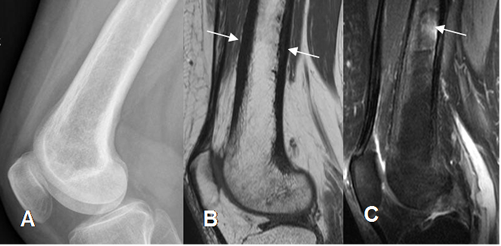

Fig 48. Enfermedad de Paget.

A: Rx lateral. Engrosamiento cortical, sin lesiones focales aparentes.

B: RM sagital en T1. Engrosamiento de la cortical del fémur, con algunas zonas hipointensas de la MO en la parte superior.

C: RM sagital en STIR. Zona hiperintensa en el tercio medio del fémur.